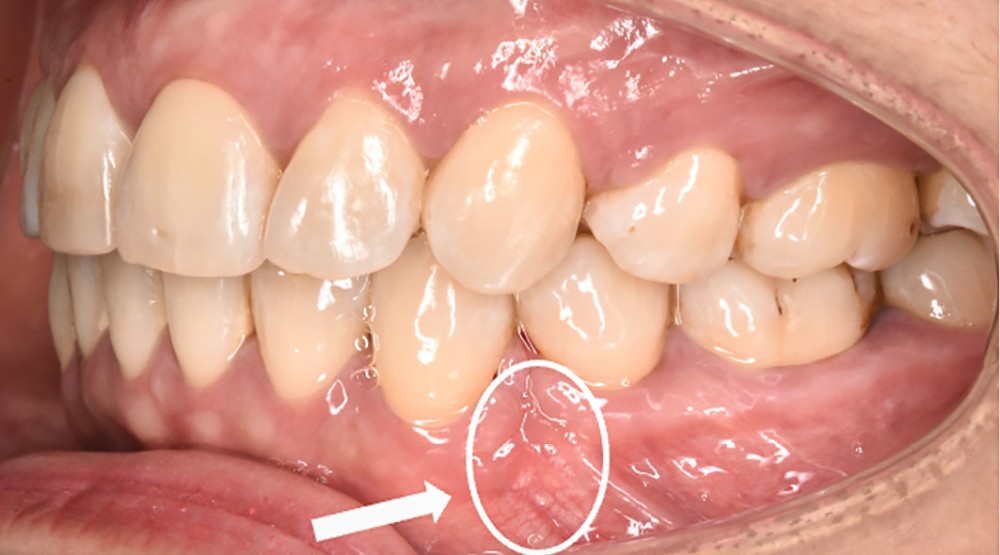

Des avulsions sont réalisées dans 15 % des traitements d’orthodontie [1], principalement en cas d’encombrement sévère ou de vestibuloversion incisive marquée. Les fentes gingivales sont des défauts parodontaux fréquemment observés lors de la fermeture orthodontique d’un espace d’avulsion (dans 35 à 100 % des cas selon les auteurs [2-7]) (fig. 1).

La fente est définie comme une invagination linéaire du tissu interdentaire en direction mésiale ou distale avec une profondeur de sondage d’au moins 1 [2] ou 2 mm [3]. Elle se présente sous forme d’un pli (ou fissure) de gencive plus ou moins sévère pouvant cacher un défaut osseux sous-jacent.